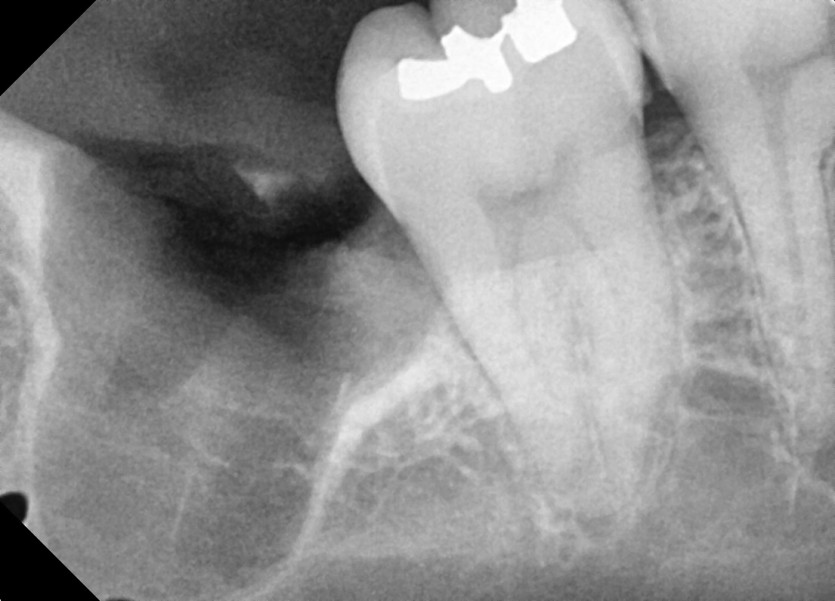

#48 사랑니 발치

구강 외과 전문의가 당일 발치했습니다.